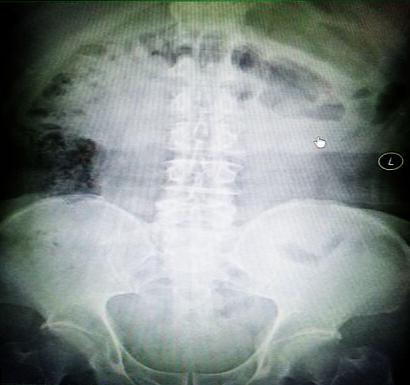

受試患者在結(jié)腸端端吻合術(shù)中,使用我司新研制產(chǎn)品達到了理想的預(yù)期效果?;颊咝g(shù)后7天、14天X光片顯影,可降解腸道支架均能按研制設(shè)計的預(yù)期時間節(jié)點保持應(yīng)有強度,術(shù)后21天X光片顯示可降解腸道支架已完全破碎,并排出體外。在整個試驗過程中,病患無任何不良反映,耐受良好。

對此,一種革命性的腸道端端吻合無縫對接手術(shù)方式又向今后大范圍的臨床推廣應(yīng)用邁出了堅實的一步!